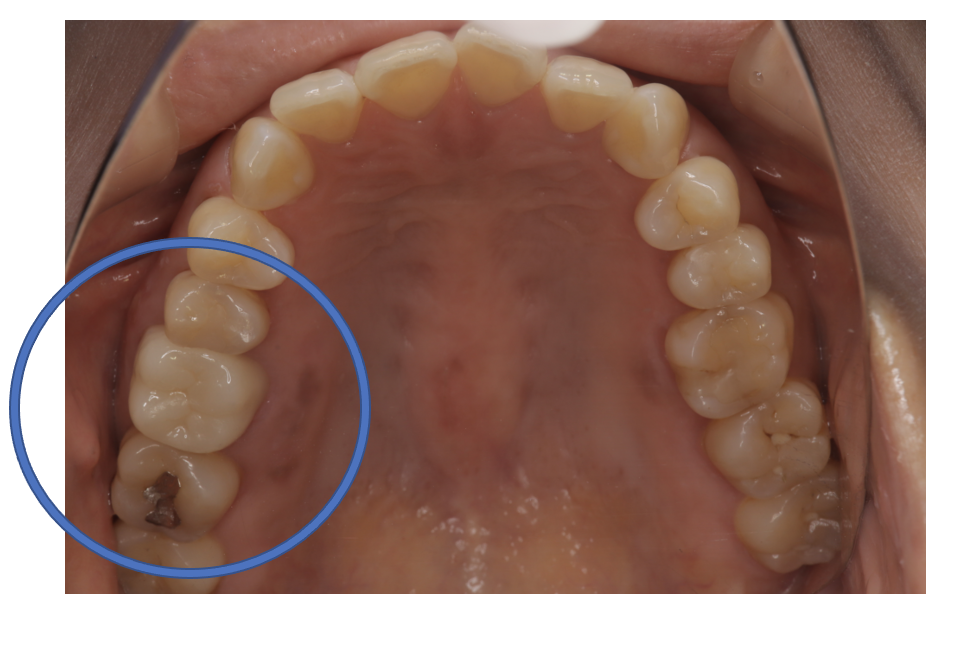

フルジルコニアCr 5 No.24

Before

| 治療方法 | フルジルコニアCr 虫歯などで失った歯質を天然歯と同じ色・質感のセラミックの一種であるジルコニア(人工ダイヤモンド)で補う治療法。 |

| 治療のデメリット | 変色がなく耐久性の高い治療ですが、歯周病や二次虫歯を予防するためには歯科医院での定期的なメインテナンスが大切です。 |

| 費用 | ¥89,000 |

| 通院回数 | 1ヶ月〜6ヶ月 |

| 備考 | 院長より プラスティック修復部の内部に虫歯が進行してしまっていたケースです。中を開けて見てみると、外から想像するよりもはるかに虫歯が広がってしまっていました。幸運にも神経を保存できたので、生きた臓器としてまだ使うことが可能です。残存歯質がかなり薄く、弱くなってしまったので、ジルコニアで被せて守ってあげています。神経が保存してあり、生きている臓器なので、これからも長く使っていけそうです。 |